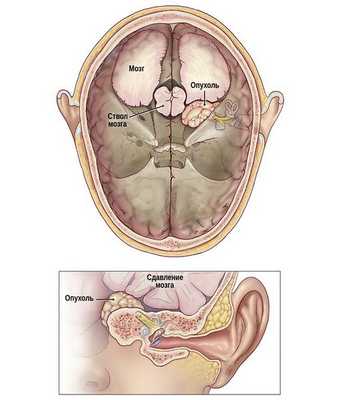

Рис. Схематичное изображение роста невриномы слухового нерва из внутреннего слухового прохода в заднюю черепную ямку со сдавление ствола головного мозга.

Патогенетически выделяют 3 стадии развития вестибулярной шванномы. В первой небольшие размеры образования (до 2,5 см) приводят к нарушению слуха (тугоухости) и вестибулярным расстройствам. Во второй новообразование вырастает до размеров грецкого ореха, оказывает давление на ствол мозга, что приводит к появлению нистагма, дискоординации движений и расстройства равновесия. В третьей стадии, когда невринома достигает размеров куриного яйца, она вызывает резкое сдавление церебральных структур, гидроцефалию, нарушения зрения и глотания. На этой стадии в тканях головного мозга происходят необратимые изменения, опухоль иноперабельна и является причиной летального исхода.